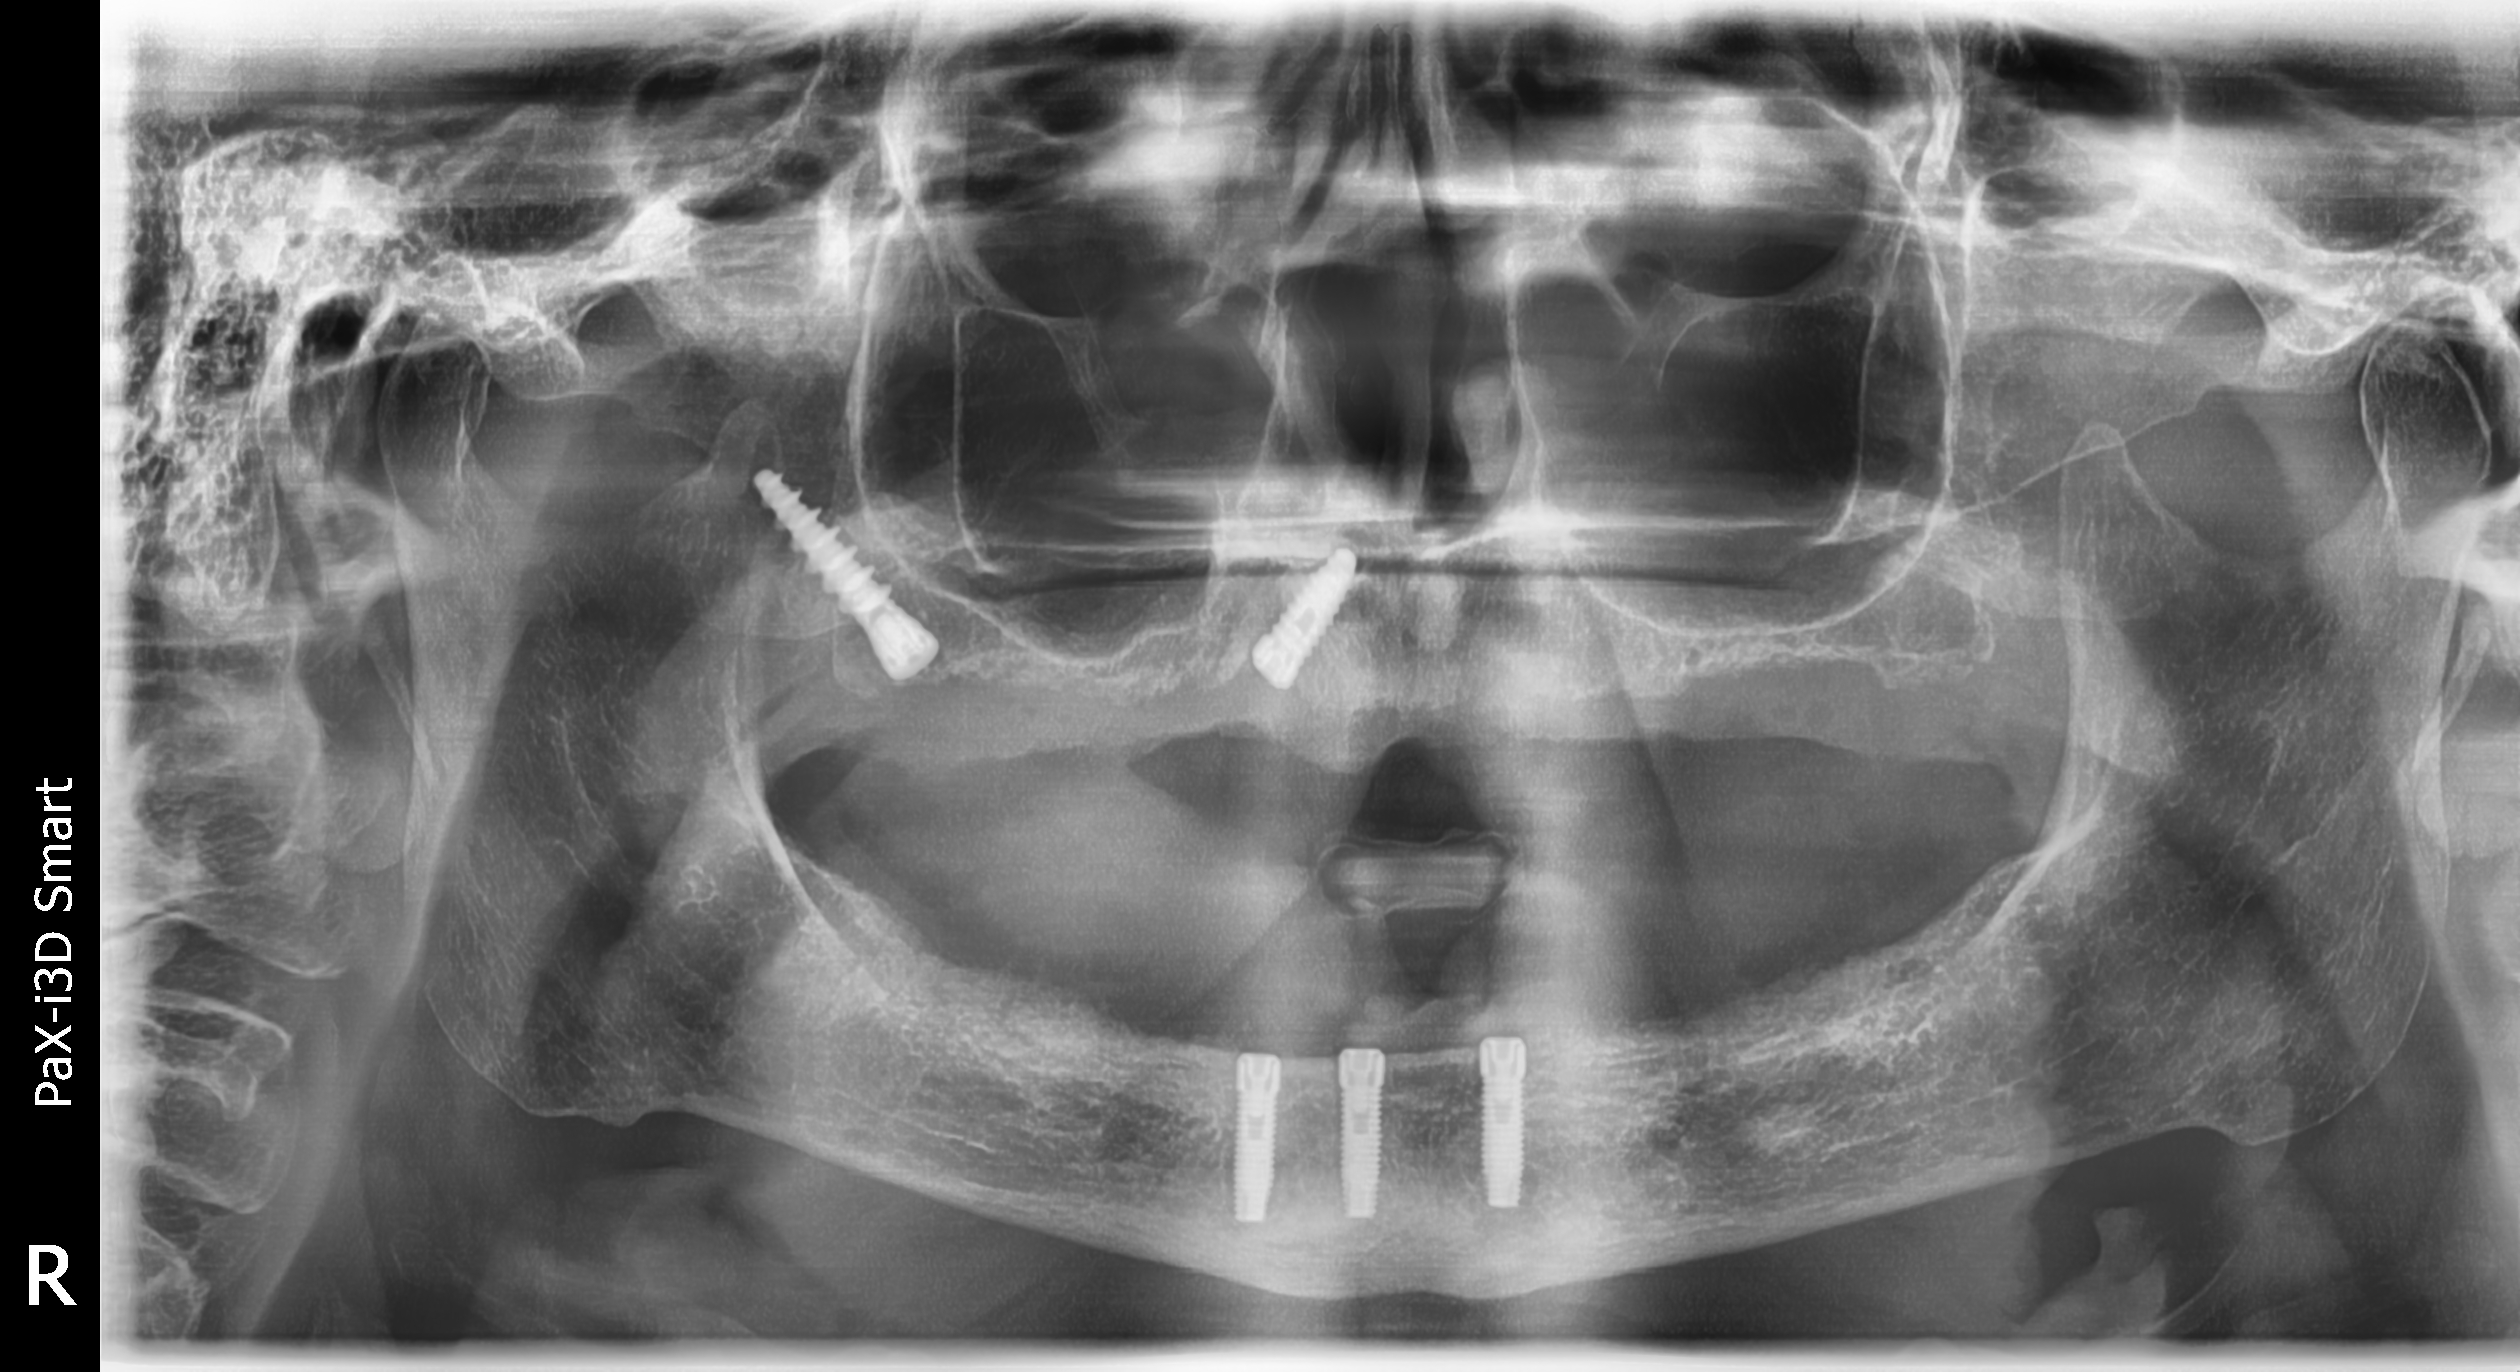

Gli impianti dentali pterigoidei sono una soluzione all’avanguardia per i pazienti che cercano una stabilità eccezionale nella sostituzione dei denti persi.

Questi impianti sono posizionati nell’area anatomica del pterigoide, nell’osso mascellare superiore, una posizione critica per garantire la loro stabilità e successo a lungo termine.

La posizione strategica degli impianti pterigoidei è ideale per pazienti che potrebbero avere una quantità insufficiente di osso mascellare in altre zone.